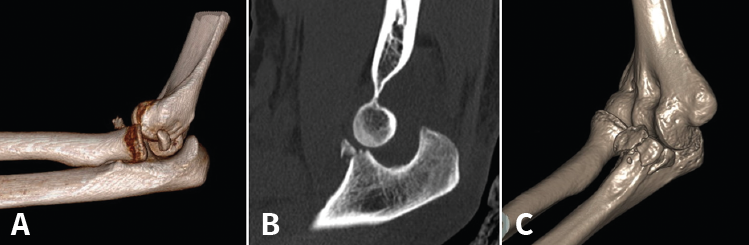

Figura 10. Correspondencias entre la clasificación de Regan y Morrey, y la clasificación de O’Driscoll.

O’Driscoll propuso una clasificación basada además en la localización y el número de fragmentos (Tabla 5). Posteriormente, observaron que en función del tamaño y la localización de los fragmentos existían asociaciones con otras lesiones y definieron 3 tipos de patrones(47,48,49,50):

- Fractura de la punta de la coronoides asociada a luxación de codo y a fractura de la cabeza del radio, la llamada tríada terrible. Se ven normalmente tras una luxación posterior o posterolateral. Se pensaba que la fractura coronoides era por avulsión, pero en realidad es por cizallamiento. Si asocia una lesión del LCL, puede llevar a una inestabilidad rotatoria posterolateral (Figura 11).

- Fractura de la faceta anteromedial de la coronoides asociada a subluxación (más que a luxación) y a avulsión del LCL del epicóndilo lateral. Es el patrón conocido como inestabilidad rotatoria posteromedial. Sucede normalmente tras un traumatismo en varo con una rotación posteromedial añadida.

- Fractura de la base de la coronoides. Asociadas a fractura-luxación de olécranon. Se han visto 2 coincidencias. Las fracturas de la base con un fragmento grande y único suelen ir asociadas a fractura-luxación anterior del olécranon y los ligamentos permanecen intactos. Si la fractura-luxación es posterior, hay conminución y va acompañada de avulsión proximal del LCL(51).

Figura 11. A: imagen en 3D de una fractura de tipo I de O’Driscoll con inestabilidad de codo, donde se observa además un fragmento de la cabeza del radio desplazado; B: imagen de tomografía axial computarizada (TAC) en un plano sagital. C: imagen de reconstrucción en 3D de una fractura de tipo II.